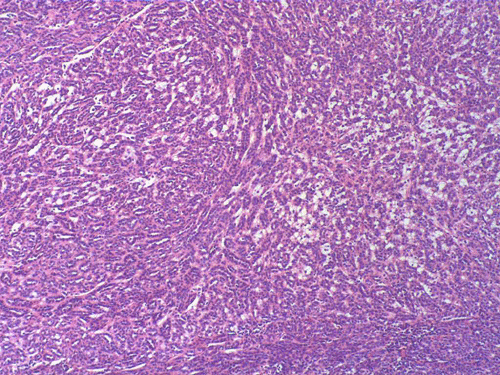

Two major patterns are revealed. In the first pattern, the tumor cells grow in a densely packed tubular pattern with mucinous content (Panel A and B). In some other areas, the tubular pattern is replaced by interlacing fascicles of spindle cells separated by mucinous pools (Panel C and D). In some areas, the spindle cells are solidly packed (Panel E). In both areas, the nuclear are bland in appearance and without significant mitotic acivity. The tumor cells, both in the spindle cell area and tubular areas are strongly positive for cytokerain AE1/AE3, cytokeratin 7, Cam5.2, and epithelial membrane antigen (EMA) respectively (Panel F, G, H and I). The tumor cells are also negative for synaptophysin (Panel J and K) and CD10 (Panel L and M). The positive cells in Panel M are residual non-neoplastic renal tubules. The Ki67 labeling (Panel N) is low (about 1-2%).

| DIAGNOSIS: Mucinous tubular and spindle cell carcinoma. |

These tumors have very characteristic histologic patterns comprised of cuboidal and spindle cells. The cuboidal cells tend to form tubular growth patterns, although trabercular and solid patterns can be identified. Sheets of spindle cells often intersperse between interconnecting tubules, leading to a biphasic appearance. The cells are characterized by eosinophilic cytoplasm, small to medium sized nuclei with little to no atypia, and occasional prominent nucleoli. The surrounding stroma is predominantly myxomatous with a bubbly quality and stains consistently with alcian blue. Studies have shown that a wide majority of MTSCC tumors are positive for epithelial membrane antigen (EMA), AE1/AE3, and cytokeratin 7. In contrast to the classic type of renal cell carcinoma, only about 15% of these tumors are positive for CD10 5. Expression of neuroendocrine markers has also been demonstrated in some tumors 6, 7. Other immunohistochemical markers may be variably positive, including E-cadherin, vimentin, and Ulex Europeus agglutinin-1 (UEA-1). These tumors have a low MIB-1 labeling index. In general, there is not a single marker that could confidently separate this tumor from other renal tumor. The final diagnosis must rest on considerations of morphological and immunohistochemical evidence.